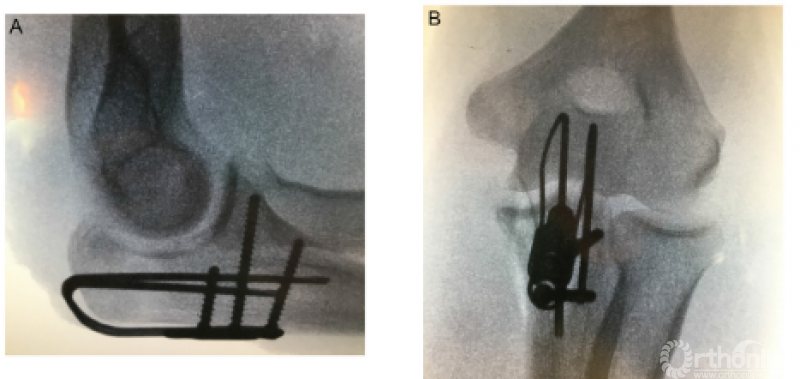

1、Lovy等采用鹰嘴雪橇板治疗Mayo II型鹰嘴骨折,在至少12个月的随访中,22例患者获得了满意的临床功能,均未取出内固定,也未出现感染或内固定相关的并发症,仅1例患者出现HO以及尺神经症状,做了关节镜下清理和尺神经前移。

1、肘关节旋转轴三维定位

国内蒋协远教授团队在世界上率先采用三维导航机器人进行肘关节旋转中心定位。TiRobot机器人导航辅助肘关节旋转中心轴定位能够极大地降低主观判断造成的旋转轴偏移,提高轴心定位精准度,减少反复透视验证的过度辐射及反复调整轴心导针的骨质破坏,避免可能的血管、神经损伤,显著减小降低术后肘关节活动阻力,并减少外固定针松动、断裂及外固定架断裂等并发症的发生率,从而整体提高治疗效果。